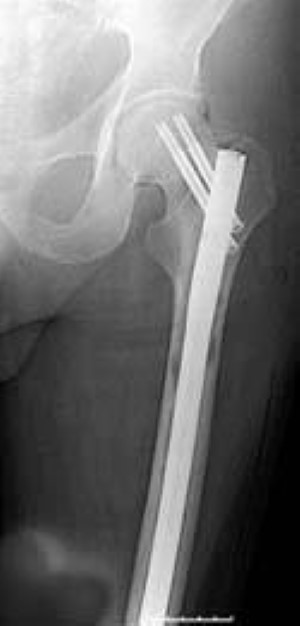

Some types of bone cancer occur primarily in children, while others affect mostly adults. It is more common in children and young adults than older adults. Read about bone cancer prognosis, treatment, symptoms, signs, survival rate, types, metastatic, and stage 4. For most fractures of the femur, a bone plate and series of screws are used to stabilize the fracture.